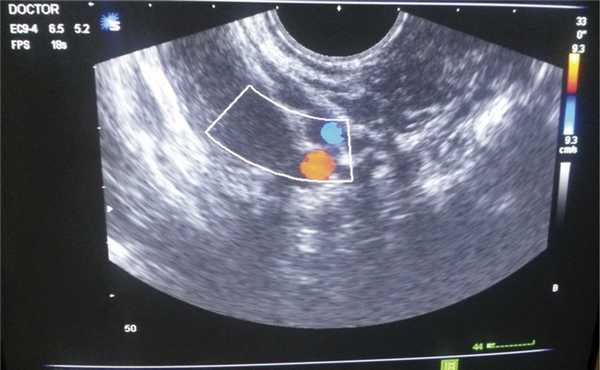

Контрольное обследование через 3 мес после операции выявило признаки рецидивирования опухоли до первоначальных размеров. При визуальном осмотре промежность не деформировна, отмечается небольшая асимметрия за счет увеличения правой ягодицы (рис. 12). МРТ выявило справа в полости малого таза с распространением от параректальной (выше ануса на 1,8 см) до паравезикальной областей солидное образование неправильной формы больших размеров, достаточно однородной структуры, с четкими неровными контурами, размером 4,8×7,4×11,8 см, с диффузным типом накопления контрастного вещества. Данное образование оказывает объемное воздействие на прямую кишку, смещая ее влево (граница между серозной оболочкой кишки и образованием местами нечеткая); образование также прилежит к матке и мочевому пузырю (между ними определяется жировая прослойка), деформируя их, и к внутренней запирательной мышце, вызывая нерезкую ее деформацию. При ультразвуковом исследовании образование аналогичных размеров, гипоэхогенной структуры, визуализируются единичные локусы кровотока (рис. 13).

Рис. 13. Допплерометрия рецидива опухоли в послеродовом периоде.